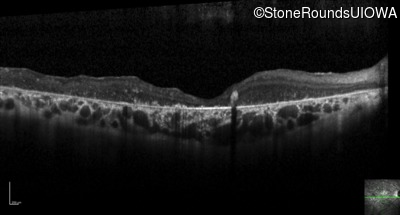

Optical Coherence Tomography - Left - 20/250 sc

Exemplar / OCT Stack